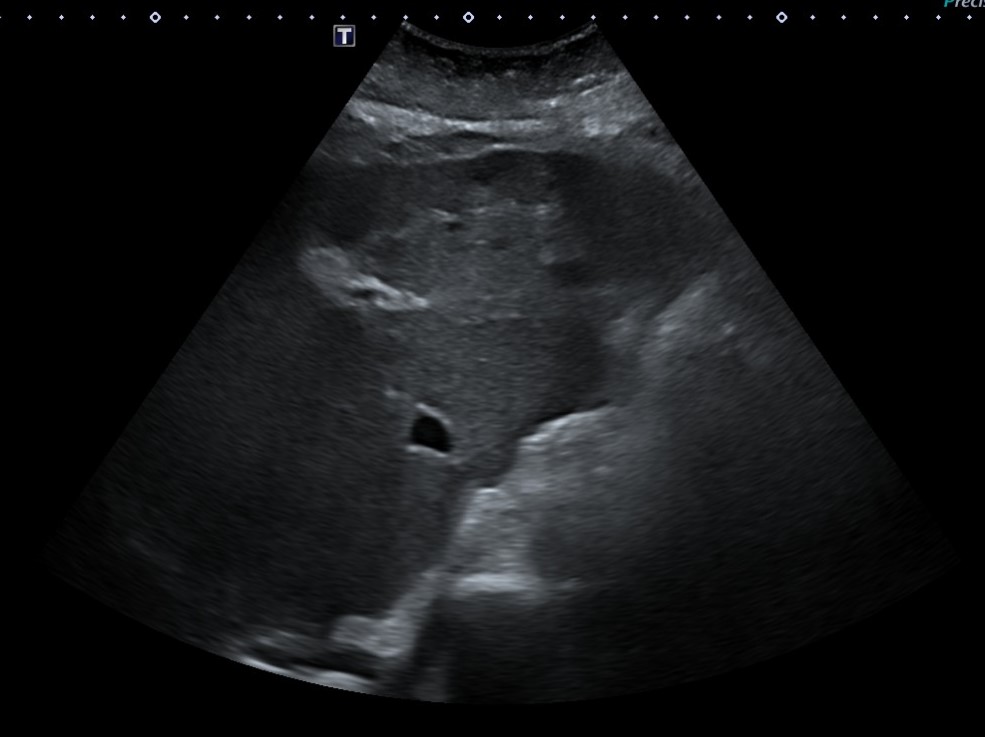

Ante resultados analíticos se realiza ecografía clínica a pie de cama. Se evidencia parénquima hepático de consistencia irregular con lesiones hipoecoicas sugestivas de metástasis tumorales. Se solicita estudio reglado.

En TC abdominal-pélvico informan:

Múltiples lesiones hipodensas hepáticas en probable relación con metástasis sin poder descartar sobreinfección de las mismas dado los datos clínicos aportados. Adenopatías retroperitoneales patológicas.